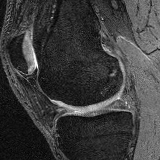

Moving Target Mono-0 Mono-5 DA-1 DA-5 Mono-200 Refer to caption Refer to caption Refer to caption Refer to caption Refer to caption Refer to caption Refer to caption Refer to caption Refer to caption Refer to caption Refer to caption Refer to caption Refer to caption Refer to caption

Figure 2:  Examples of knee MRI registration (top) and brain MRI segmentation (bottom) results. Top: The first two columns are the moving image/segmentation and the target image/segmentation followed by the warped moving images (with deformation grids)/segmentations by different models. Bottom left to right: original image, manual segmentation, and predictions of various models. Mono-i𝑖i and DA-i𝑖i represent the mono- and DA models with i𝑖i manual segmentations respectively.

Knee MRI experiment: We test our method on 3D knee MRIs from the Osteoarthritis Initiative (OAI) 111https://nda.nih.gov/oai/ and corresponding segmentations of femur and tibia as well as femoral and tibial cartilage [1]. From a total of 507 labeled images, we use 200 for training, 53 for validation, and 254 for testing. To test registration performance we use 10,000 random image pairs from the test set. All images are affinely registered to an atlas built from the training images, resampled to isotropic spacing of 1mm, cropped to 160×160×160160160160160\times 160\times 160 and intensity normalized to [0,1]. In addition, right knee images are flipped to be consistent with left knees. For training, the loss weights are λr=20,000subscript𝜆𝑟20000\lambda_{r}=20,000, λa=3subscript𝜆𝑎3\lambda_{a}=3, and λsp=3subscript𝜆𝑠𝑝3\lambda_{sp}=3 based on approximate hyper-parameter tuning. Note that when computing rsubscript𝑟\mathcal{L}_{r} from the displacements, the image coordinates are scaled to [-1, 1] for each dimension following the convention in the interpolation function of PyTorch.

Results: All trained networks are evaluated using Dice overlap scores between predictions and the manual segmentations for the segmentation network, or between the warped moving segmentations and the target segmentations for the registration network. Tabs. 1 and 2 show results for the knee and brain MRI experiments respectively in Dice scores (%). Fig. 2 shows examples of knee MRI registrations and brain MRI segmentations.

Qualitative results: DA achieves more anatomically consistent registrations than the mono-networks on the knee (Fig. 2) and Brain MRI samples (see supplementary material).